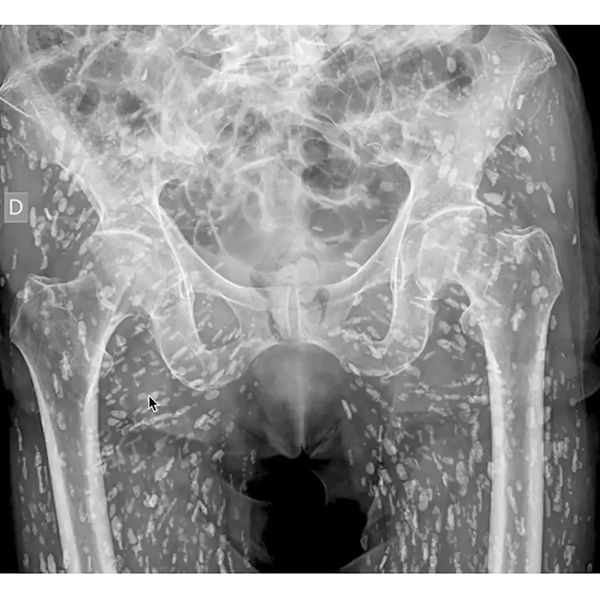

米フロリダ州の救急医がXに投稿…「最も異常なX線写真」が示す教訓

どうしてこんなことに?!(サム・ガリ医師のXから)